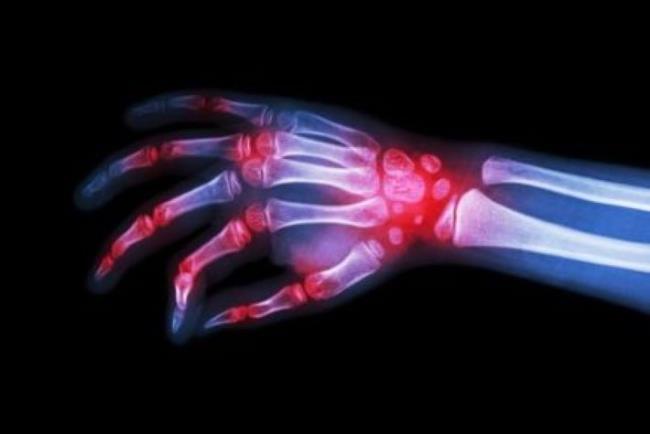

סימפוני שייכת לקבוצת תרופות הנקראות "חוסמי TNF". התרופה משמשת במבוגרים לטיפול בדלקת מפרקים שגרונית (Rheumatoid arthritis), בדלקת מפרקים ספחתית (Psoriatic arthritis) ובדלקת חוליות מקשחת (Ankylosis Spondylitis). דלקת מפרקים אידיופטית של גיל הילדות, דלקת כיבית של המעי הגס, בדרגת חומרה בינונית עד חמורה, ותחת תנאים מסויימים.

סימפוני פועלת באמצעות חסימת חלבון שנקרא TNF-αהמעורב בתהליכים דלקתיים בגוף. חסימתו גורמת להפחתת המצב הדלקתי בגוף.